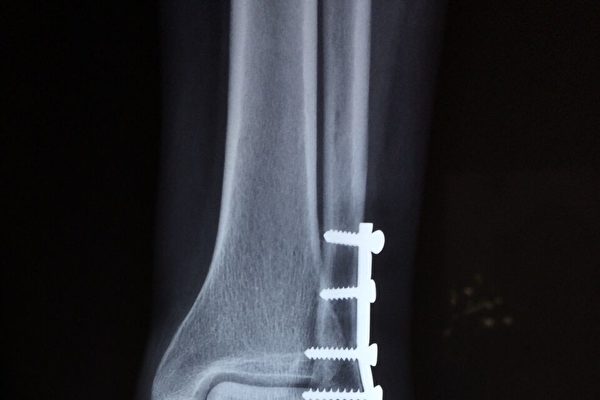

非髋部骨折占所有脆性骨折的三分之二以上,包括股骨、骨盆、锁骨或小腿骨折。

调查发现,在髋骨骨折后的一年中,男性死亡风险高出33%,女性则高出20%。而对于股骨或骨盆骨折,一年的超额死亡率在20%至25%之间。

在髋骨骨折发生10年后,患者仍旧存在着明显的死亡风险,而非髋骨骨折带来的风险约为5年。